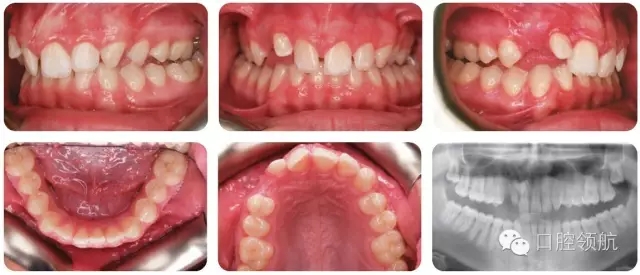

該患者錯(cuò)牙合特點(diǎn)(圖2.38)是什么?

● II類2分類切牙關(guān)系。

● 覆牙合較深。

● 中線不調(diào)(上中線右偏2mm)。

● 后牙近中尖對尖關(guān)系(雙側(cè))。

● 上牙弓中度擁擠。

● UR3未萌,可能與UR2異位。